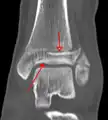

A triplane fracture of the ankle as seen on CT

CT

CT scans may be indicated when there is concern for a highly comminuted fracture or a fracture involving the joint surface.[9] This imaging may be used for surgical planning.

- Triplane fractures are a special type of fracture that involves the immature skeleton. It has a coronal plane in the metaphysis, an axial plane in the physis, and a sagittal plane in the epiphysis.[14]